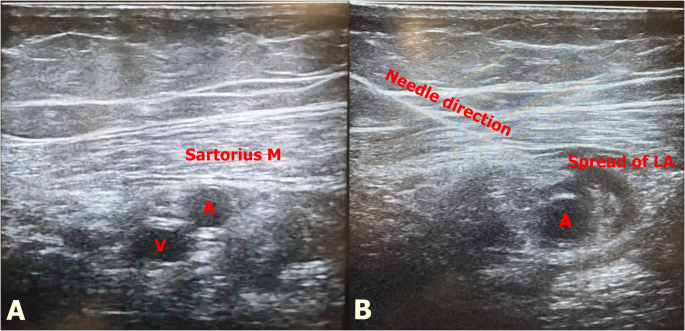

The block procedure was performed after the surgery was completed. All adductor canal blocks were performed by two experienced anesthesiologists with advanced clinical expertise in regional anesthesia. After ensuring aseptic conditions, a high-frequency linear ultrasound probe (GE ML6-15-D Matrix Linear, Boston, USA) was covered with a sterile sheath, and a 100 mm block needle (Stimuplex Ultra®, Braun, Melsungen, Germany) was used. The linear ultrasound probe was placed medial to the patella, and the probe was advanced cephalad to visualize the femoral artery, the adductor hiatus, and the apex of the femoral triangle. Then, 5 ml of saline was injected under ultrasound guidance into the midpoint of the adductor canal to confirm the block site (Fig. 2). Then, local anesthetic solution containing bupivacaine at 0.25% concentration was administered as 20 ml in Group 20, 30 ml in Group 30, and 40 ml in Group 40.

A Adductor canal sonographic anatomy. Sartorius Muscle, A; artery, V; vein. B Sonographic anatomy of block. Needle direction, and spread of local anesthetic during block performing. A; artery